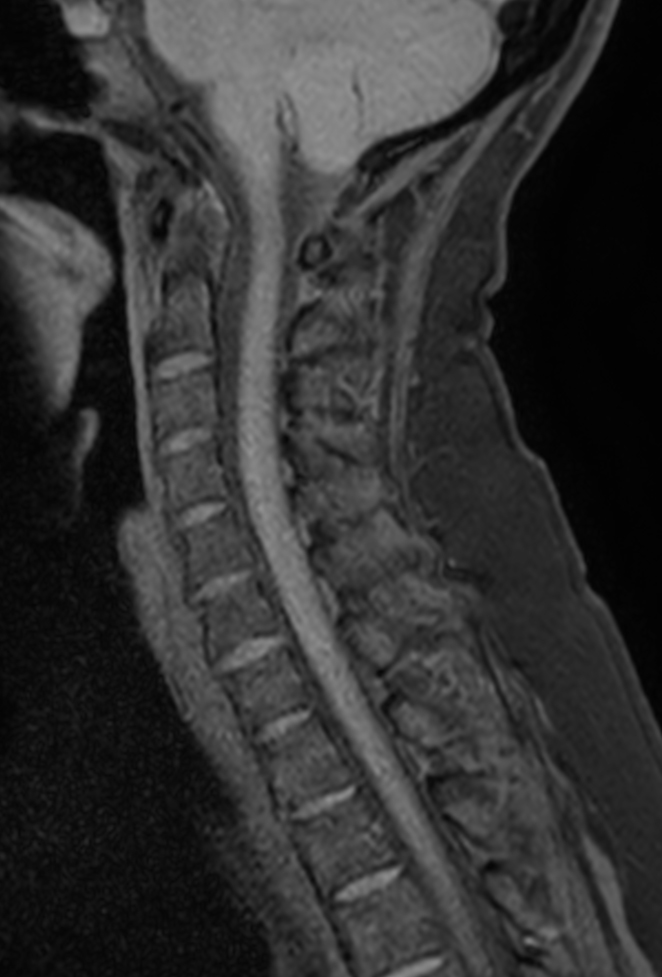

Sagittal T1w TSE mDIXON XD (In Phase)